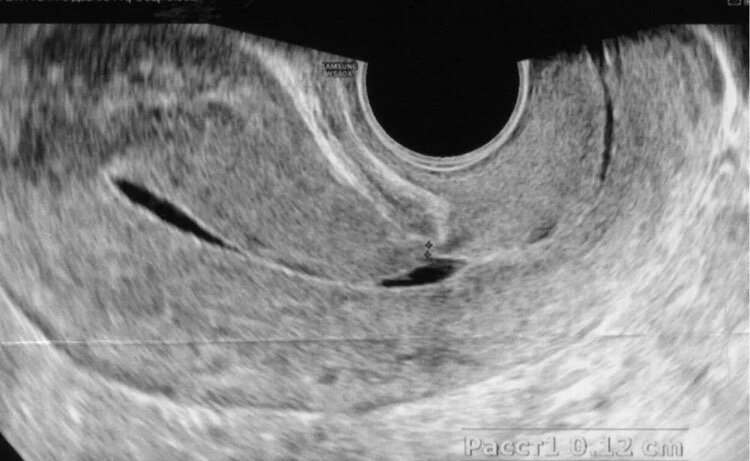

Шейка матки наботовы кисты. Удаление наботовых кист